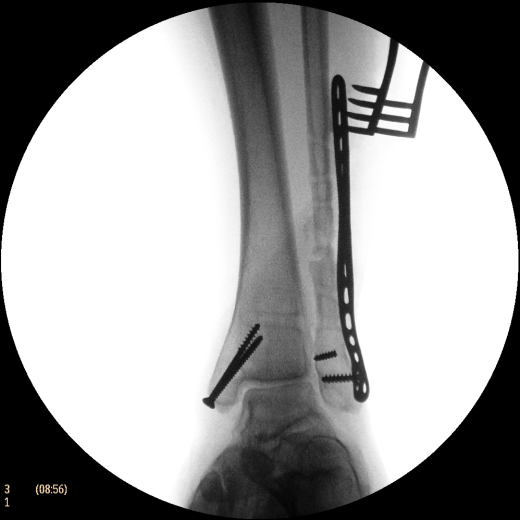

Система Philips BV Endura, рассчитанная на выполнение рутинных задач, расширяет возможности процедур на сосудах. Компактный размер 9-дюймового усилителя изображения обеспечивает маневренность для ортопедии и травматологии, а 12-дюймовый обеспечивает превосходный охват для выполнения сосудистых процедур, урологии и общей хирургии. Кроме того, мы увеличили угол поворота C-дуги до 135°, чтобы дать возможность получения проекций, необходимых для большинства процедур на сосудах.

Полностью цифровая цепь формирования изображений с матрицей 1024х1024 использует передовые средства шумоподавления и двумерного подчеркивания контуров для создания изображений с высоким качеством.